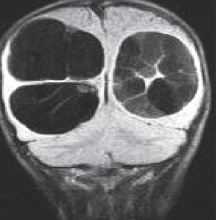

Кисты средней линии – киста прозрачной перегородки (cavum septi pellucidi), полость Верге (cavum Vergae) и киста промежуточного паруса (cavum veli interpositi) – являются нормальными структурами головного мозга плода. В течение 6 месяцев после рождения у большинства людей они запустевают, но могут и сохраниться, визуализируясь при этом на МРТ головного мозга. По-видимому, эти полости не имеют клинического значения и относятся к случайным находкам при томографии. Киста прозрачной перегородки (еще называют V желудочком) является медиальной стенкой боковых желудочков и ограничена спереди коленом мозолистого тела, сверху мозолистым телом и сзади столбами свода . Полость Верге представляет собой продолжение кисты прозрачной перегородки кзади и расположена между телами желудочков . Обычно обе кисты сочетаются. Киста промежуточного паруса расположена в крыше III желудочка (tela choroidea), между треугольниками боковых желудочков на уровне отверстий Монро. Она ограничена сверху мозолистым телом, cзади цистерной четверохолмия и снизу III желудочком.